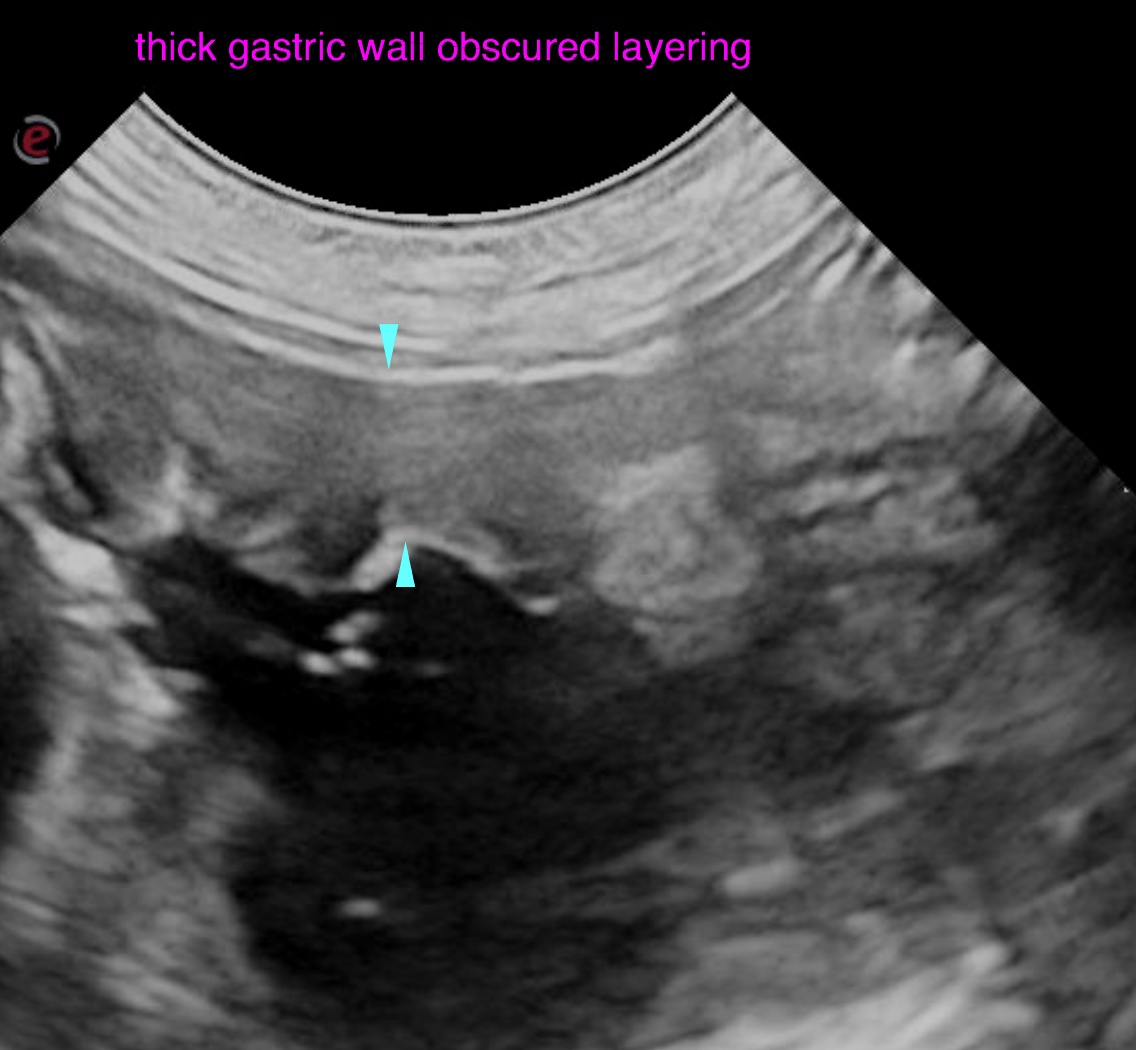

The left and right lobe of the pancreas are embedded in a slightly hyperechoic mesentery, but within normal limits for size, shape and echoarchitecture.  The gastric wall presents moderate generalized wall thickening emphasizing the submucosal layer. The interrugal wall thickness is up to 5 mm. The wall layering is moderately obscured. The mucosal surface is slightly irregular. A moderate amount of fluid is present within the stomach. The surrounding mesentery is mildly increased in echogenicity with slightly ill defined echotexture. The stomach is hypomotile. The duodenum is slightly dilated with fluid, presents hypermotility and mucosal fogging. The wall layering is witho normal limits. The jejunum presents similar changes as the duodenum. There is no obstructive pattern of the digestive tract.